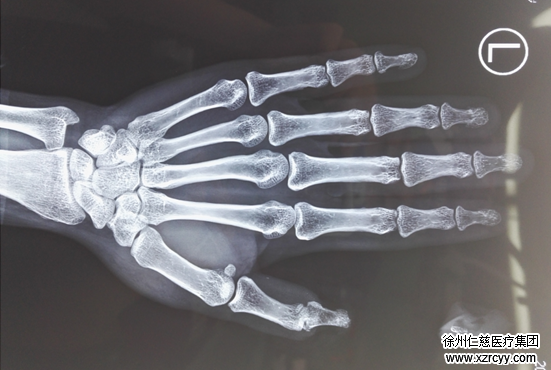

术前检查

betway在线登陆手外一病区当日接诊医生李刚说“患者受伤4小时来院,其左手大拇指近节脱套性离断,两侧血管神经自近端长段抽出。”经过相关检查和准备,小娜被推入手术室,接受断指再植手术。